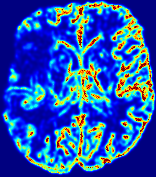

Figure 3: PIANO feature maps for one stroke patient, where the lesion is located in the left hemisphere. Top row: segmented stroke lesion region (white) on different slices, obtained from ISLES 2017. The corresponding slices for the PIANO feature maps are shown in the following rows.

For a better insight into an estimated velocity field 𝐕𝐕{\bf{V}} and diffusion field 𝐃𝐃{\bf{D}}, we compute the following maps: (1) 𝐕rgbsubscript𝐕𝑟𝑔𝑏{\bf{V}}_{rgb}: Color-coded orientation map of 𝐕=(Vx,Vy,Vz)T𝐕superscriptsuperscript𝑉𝑥superscript𝑉𝑦superscript𝑉𝑧𝑇{\bf{V}}=(V^{x},V^{y},V^{z})^{T}, obtained by normalizing 𝐕𝐕{\bf{V}} to unit length and mapping its 3 components to red, green, blue respectively; (2) 𝐕2subscriptnorm𝐕2\|{\bf{V}}\|_{2}: 222 norm of 𝐕𝐕{\bf{V}}; (3) D𝐷D: scalar field in Eq. 5.

Fig. 3 and Fig. 4 show the PIANO feature maps estimated from two ISLES 2017 patients: all are highly consistent with the lesion in both cases. Details of the blood flow trajectories are revealed in 𝐕rgbsubscript𝐕𝑟𝑔𝑏{\bf{V}}_{rgb} by the ridged patterns and the sharp changes of colors in the unaffected (right) hemisphere, while the flat patterns appearing within the lesion provide little directional information about the velocity and indicate low velocity magnitudes. Velocity magnitudes are more directly visualized via 𝐕2subscriptnorm𝐕2\|{\bf{V}}\|_{2}, from which one can easily locate the lesion where 𝐕2subscriptnorm𝐕2\|{\bf{V}}\|_{2} is low. D𝐷D also indicates lower diffusion values in the lesion, though with less contrast potentially due to the fact that it captures the accumulated effect of CA diffusion at the voxel-level.